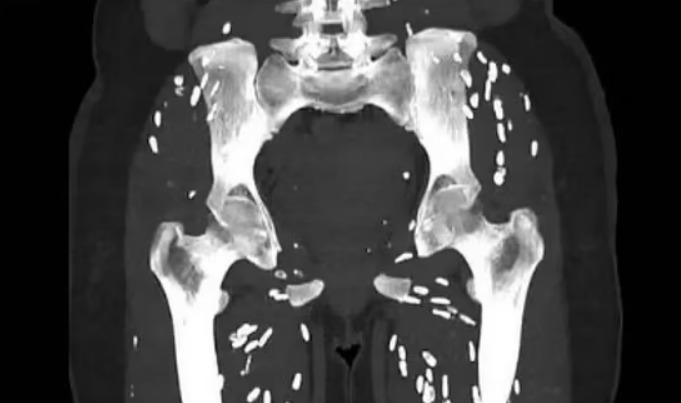

Dr Sam Ghali, një mjek i kujdesit urgjent nga Universiteti i Floridës , shkroi në mediat sociale për të ndarë një imazh të një pacienti me shenja treguese të një infeksioni parazitar të quajtur cisticerkozë dhe demete e konsumimit te mishit te derrit.

Cisticerkoza ndodh kur larvat e një lloji të krimbit të shiritit hyjnë në inde si muskuli apo edhe truri.

Ata formojnë një kist të fortë të kalcifikuar që mund të ndihet si gunga nën lëkurë dhe ndizet si nyje të bardha ovale ‘kokrra orizi’ në skanimet mjekësore.